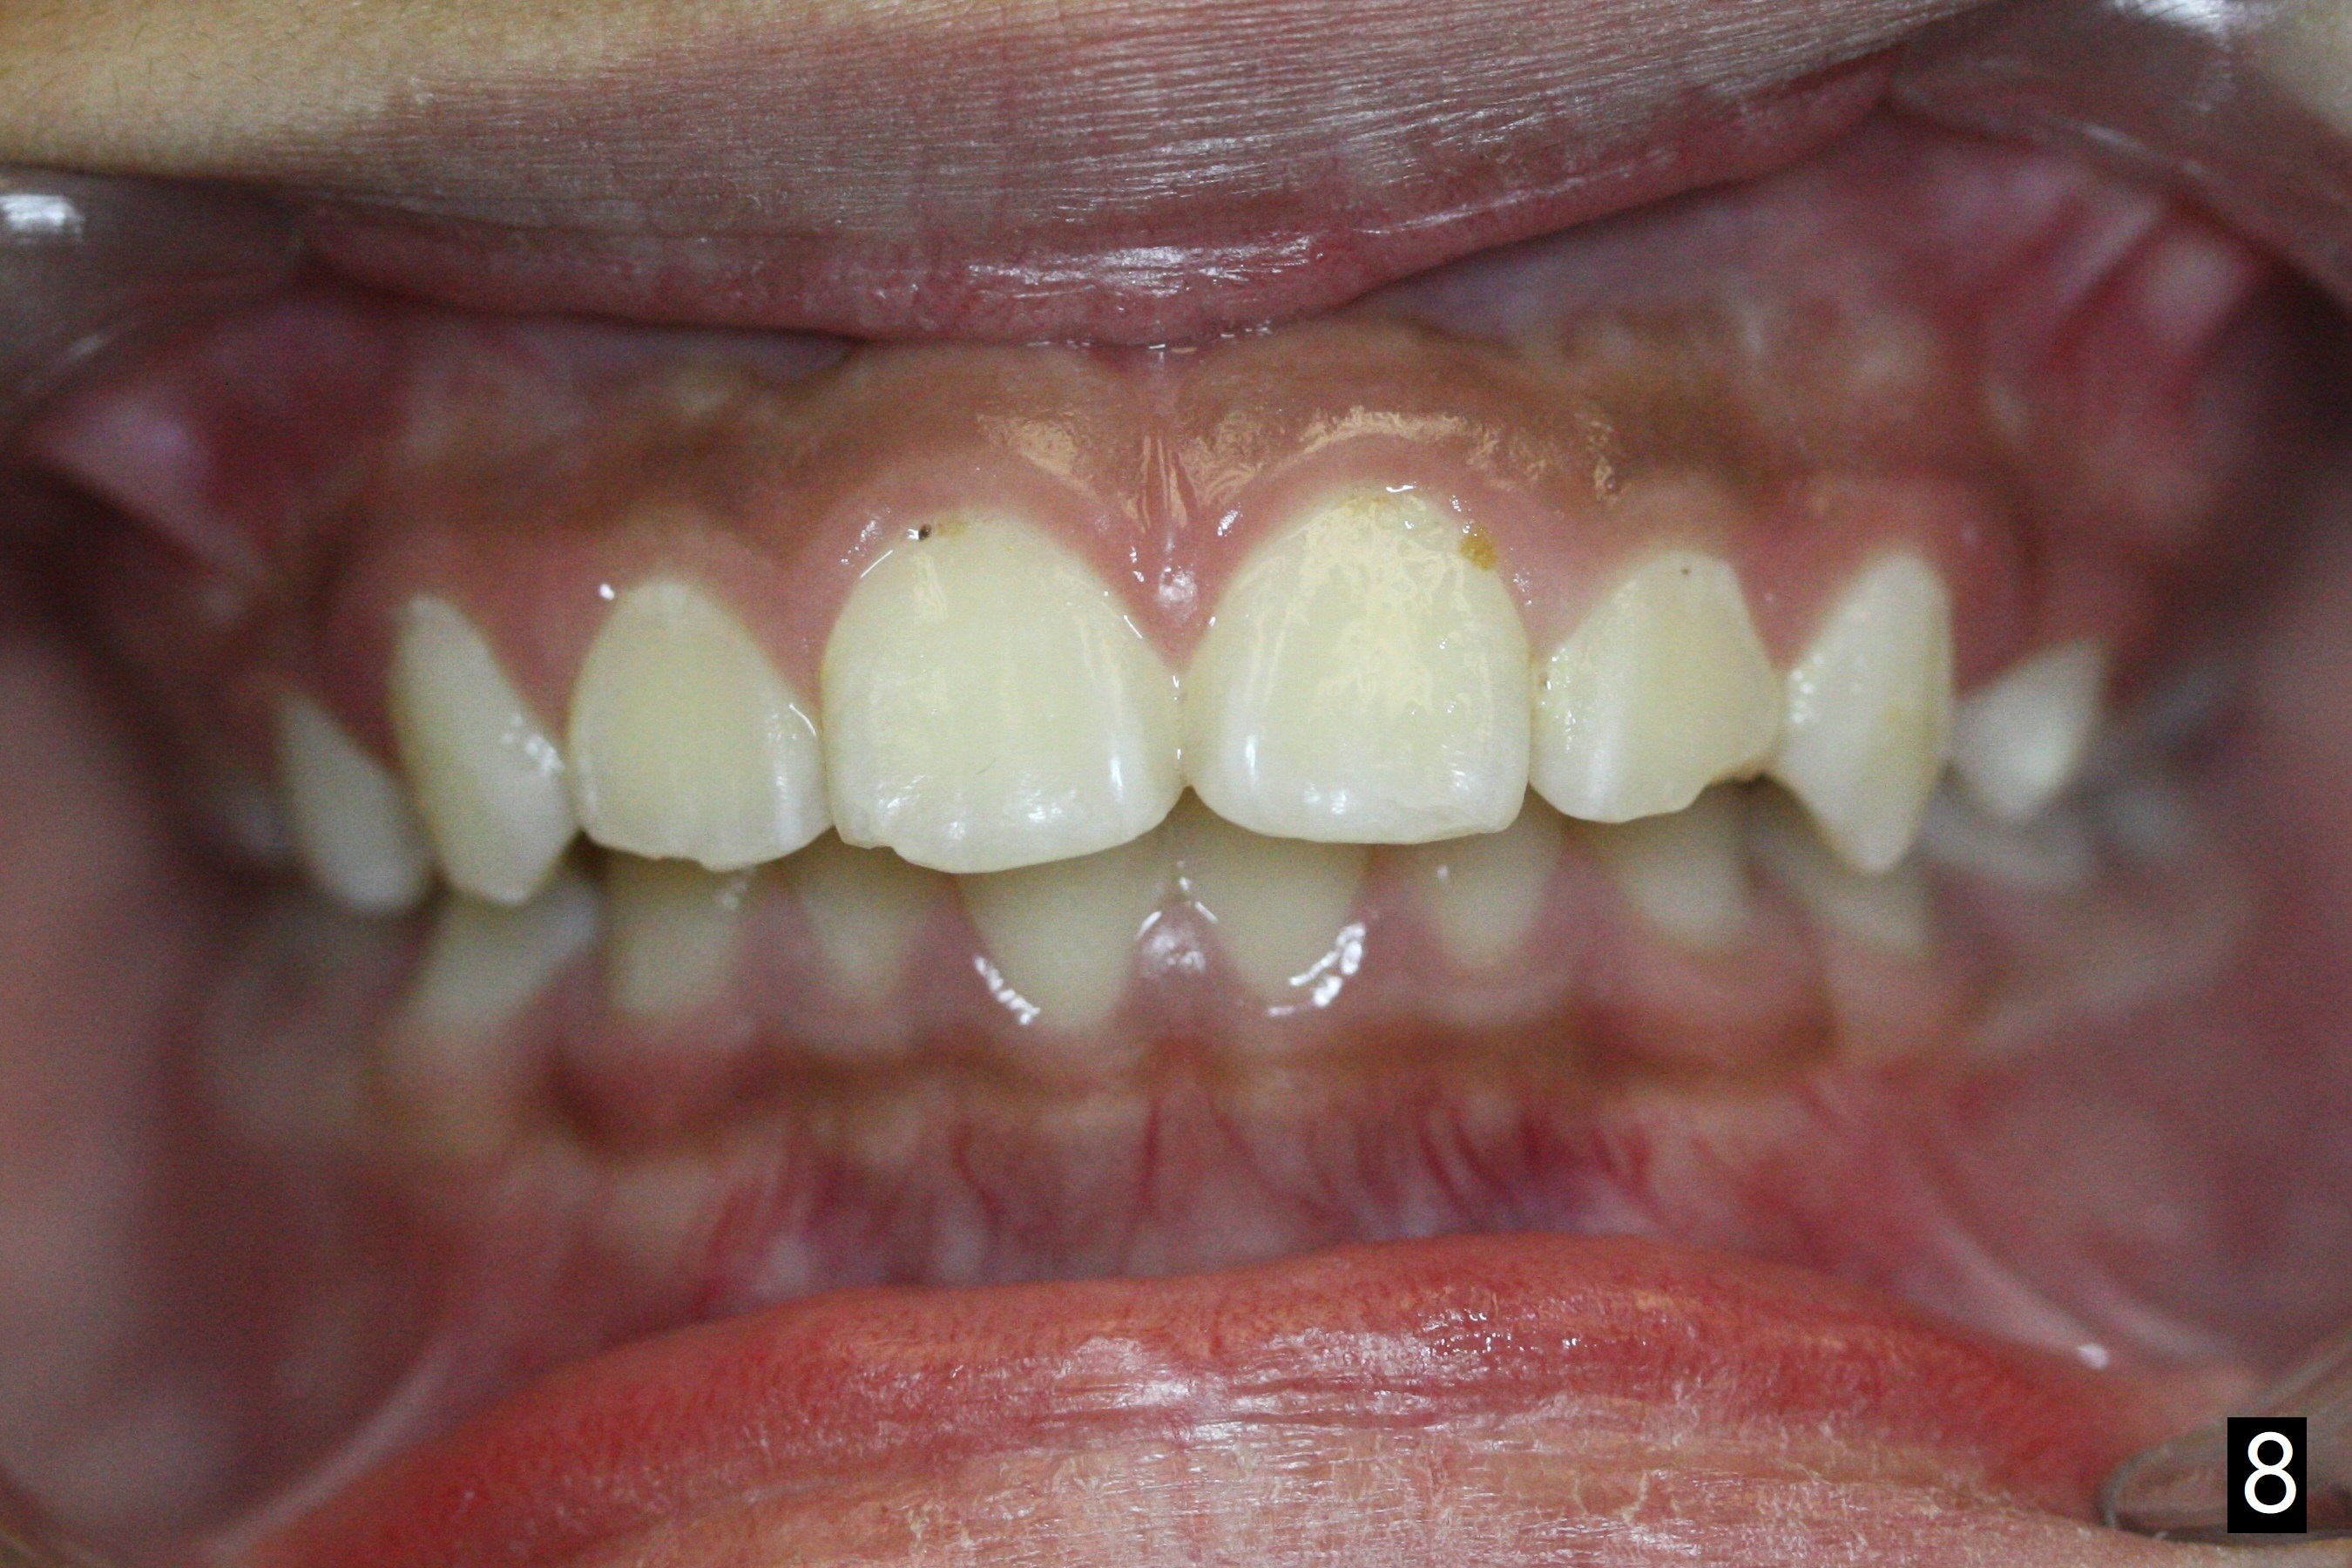

The mother of a 10-year-7-month old man requests treatment for the crowding lower incisors (Fig.14). The canines and molars are Class II by a half of a tooth (Fig.7,9,10,12). The dentition is mixed with E retention (Fig.13,14,16). Orthodontic treatment will start before E exfoliation for alignment and establishment of Class I occlusion as much as possible by distalizing U6s. Fine adjustment for intedigitation will be made when E exfoliate.